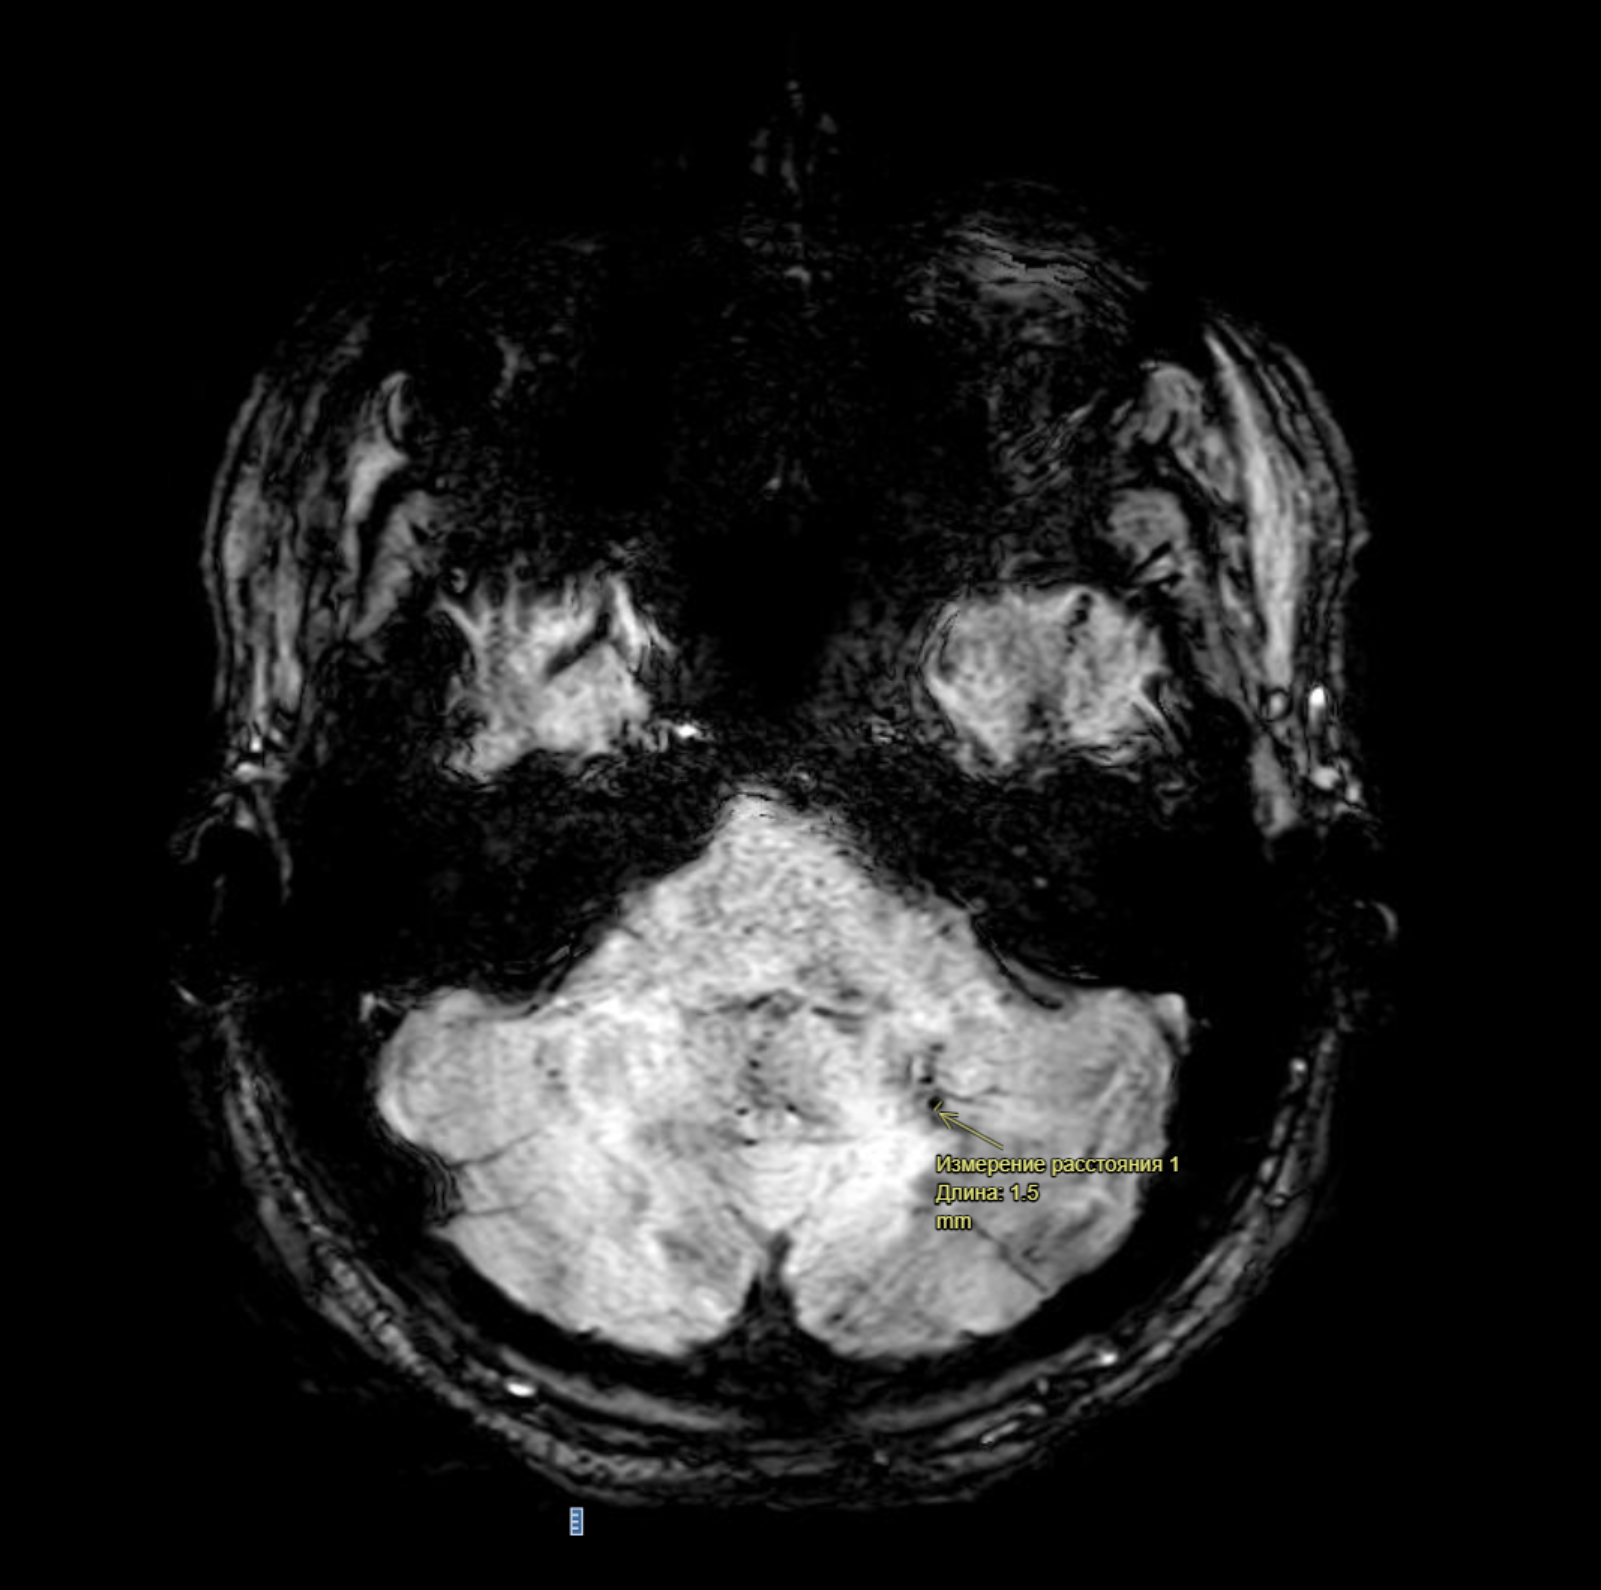

В структуре левой гемисферы мозжечка визуализируется тонкая сосудистая структура, распадающаяся на мелкую сеть по типу "метелки", гипоинтенсивного на SWI, Т1-ВИ, изоинтенсивного на Т2-ВИ сигнала, диаметром до 1,5 мм. Перифокальных изменений, в том числе геморрагических не выявлено.

Разберем, что это означает. Из описания «В структуре левой гемисферы мозжечка визуализируется тонкая сосудистая структура, распадающаяся на мелкую сеть по типу "метелки", гипоинтенсивного на SWI, Т1-ВИ, изоинтенсивного на Т2-ВИ сигнала, диаметром до 1,5 мм. Перифокальных изменений, в том числе геморрагических не выявлено».

Пояснение: Венозная ангиома – это венозная аномалия развития, которая может быть разным размеров давать различную клиническую картину. В данном случае она находится в структуре левой гемисферы мозжечка, мелких размеров 1,5 мм, без каких-либо изменений окружающих тканей и кровоизлияний (см.рис 1).